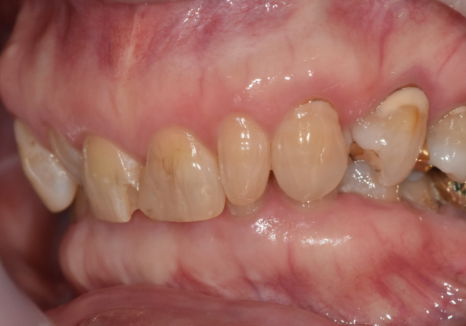

이 환자분은 70대 여성입니다.

젊을 때부터 앞니 사이가 벌어져 있었고

그 틈을 레진으로 메워 사용해 오셨다고 해요.

처음에는 괜찮았지만 나이가 들며

레진이 깨지고 떨어지는 일이 반복되자

“이번에는 제대로 고쳐보고 싶다”며 내원하셨습니다.

입안을 자세히 보니

앞니 사이를 메운 레진이 깨져 있었고,

그 양옆 작은 앞니가

다른 치아보다 눈에 띄게 작았습니다.

250304

이렇게 주변 치아보다 유난히 작은 치아를

‘왜소치’라고 부릅니다.

왜소치는 크기가 작다 보니

그 주변으로 공간이 남기 쉽고,

결국 앞니 사이가 더 벌어져 보이는 원인이 됩니다.